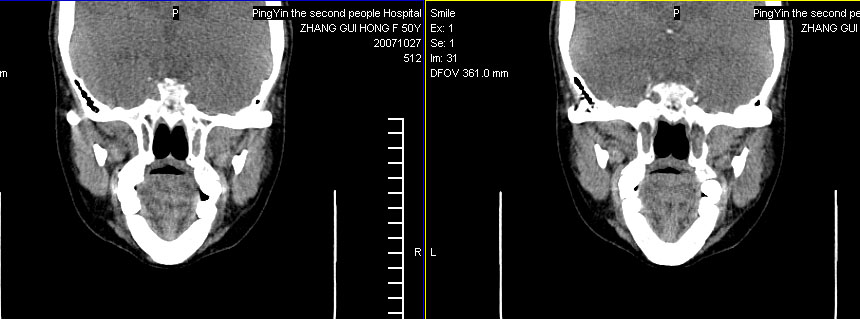

标题: CT10219:蝶鞍区有无异常?

女。50岁.头疼恶心半月余.双上颌窦区压疼明显,曾有高血压.现基本控制.

有问题,双侧侧脑室扩大,感觉鞍区有肿块,建议增强扫描.

感觉鞍区异常,建议增强扫描.